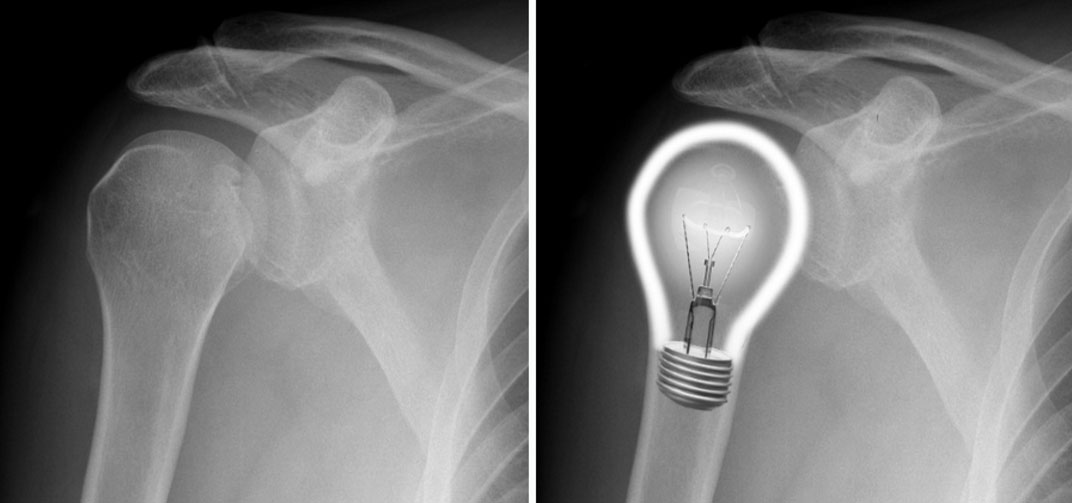

Posterior omuz çıkığında sadece omuz ön-arka radyografi ile tanı koymak zordur. Lateral grafiler çekilmesi gerekir. Anterior posterior grafideki en değerli bulgu yanan lamba görüntüsüdür.

Humerus başı posteriora yer değiştirdiğinden humerus boynu üzerinde yanan bir lamba gibi görüntü verir. Ancak glenohumeral ilişki normal gibi göründüğü için çıkık atlanabilir.

Aslında dikkatli incelenediğinde humerus başı ve glenoid arasındaki eliptik kesişim kaybolmuştur . Bu hastalarda tanı için mutlaka diğer omuz grafileri aksiller ve skapula Y grafilerinin çektirilmesi gerekmektedir. Aksiler ve skapula Y grafisinde humerus başının posterior yerleşimde olduğunu gösterir. Ancak bu grafilerin çektirilemediği durumlarda humerus başı glenoid ilişkisi ve eşlik eden diğer patolojilerin tanımlanması amacıyla BT çekilebilir.